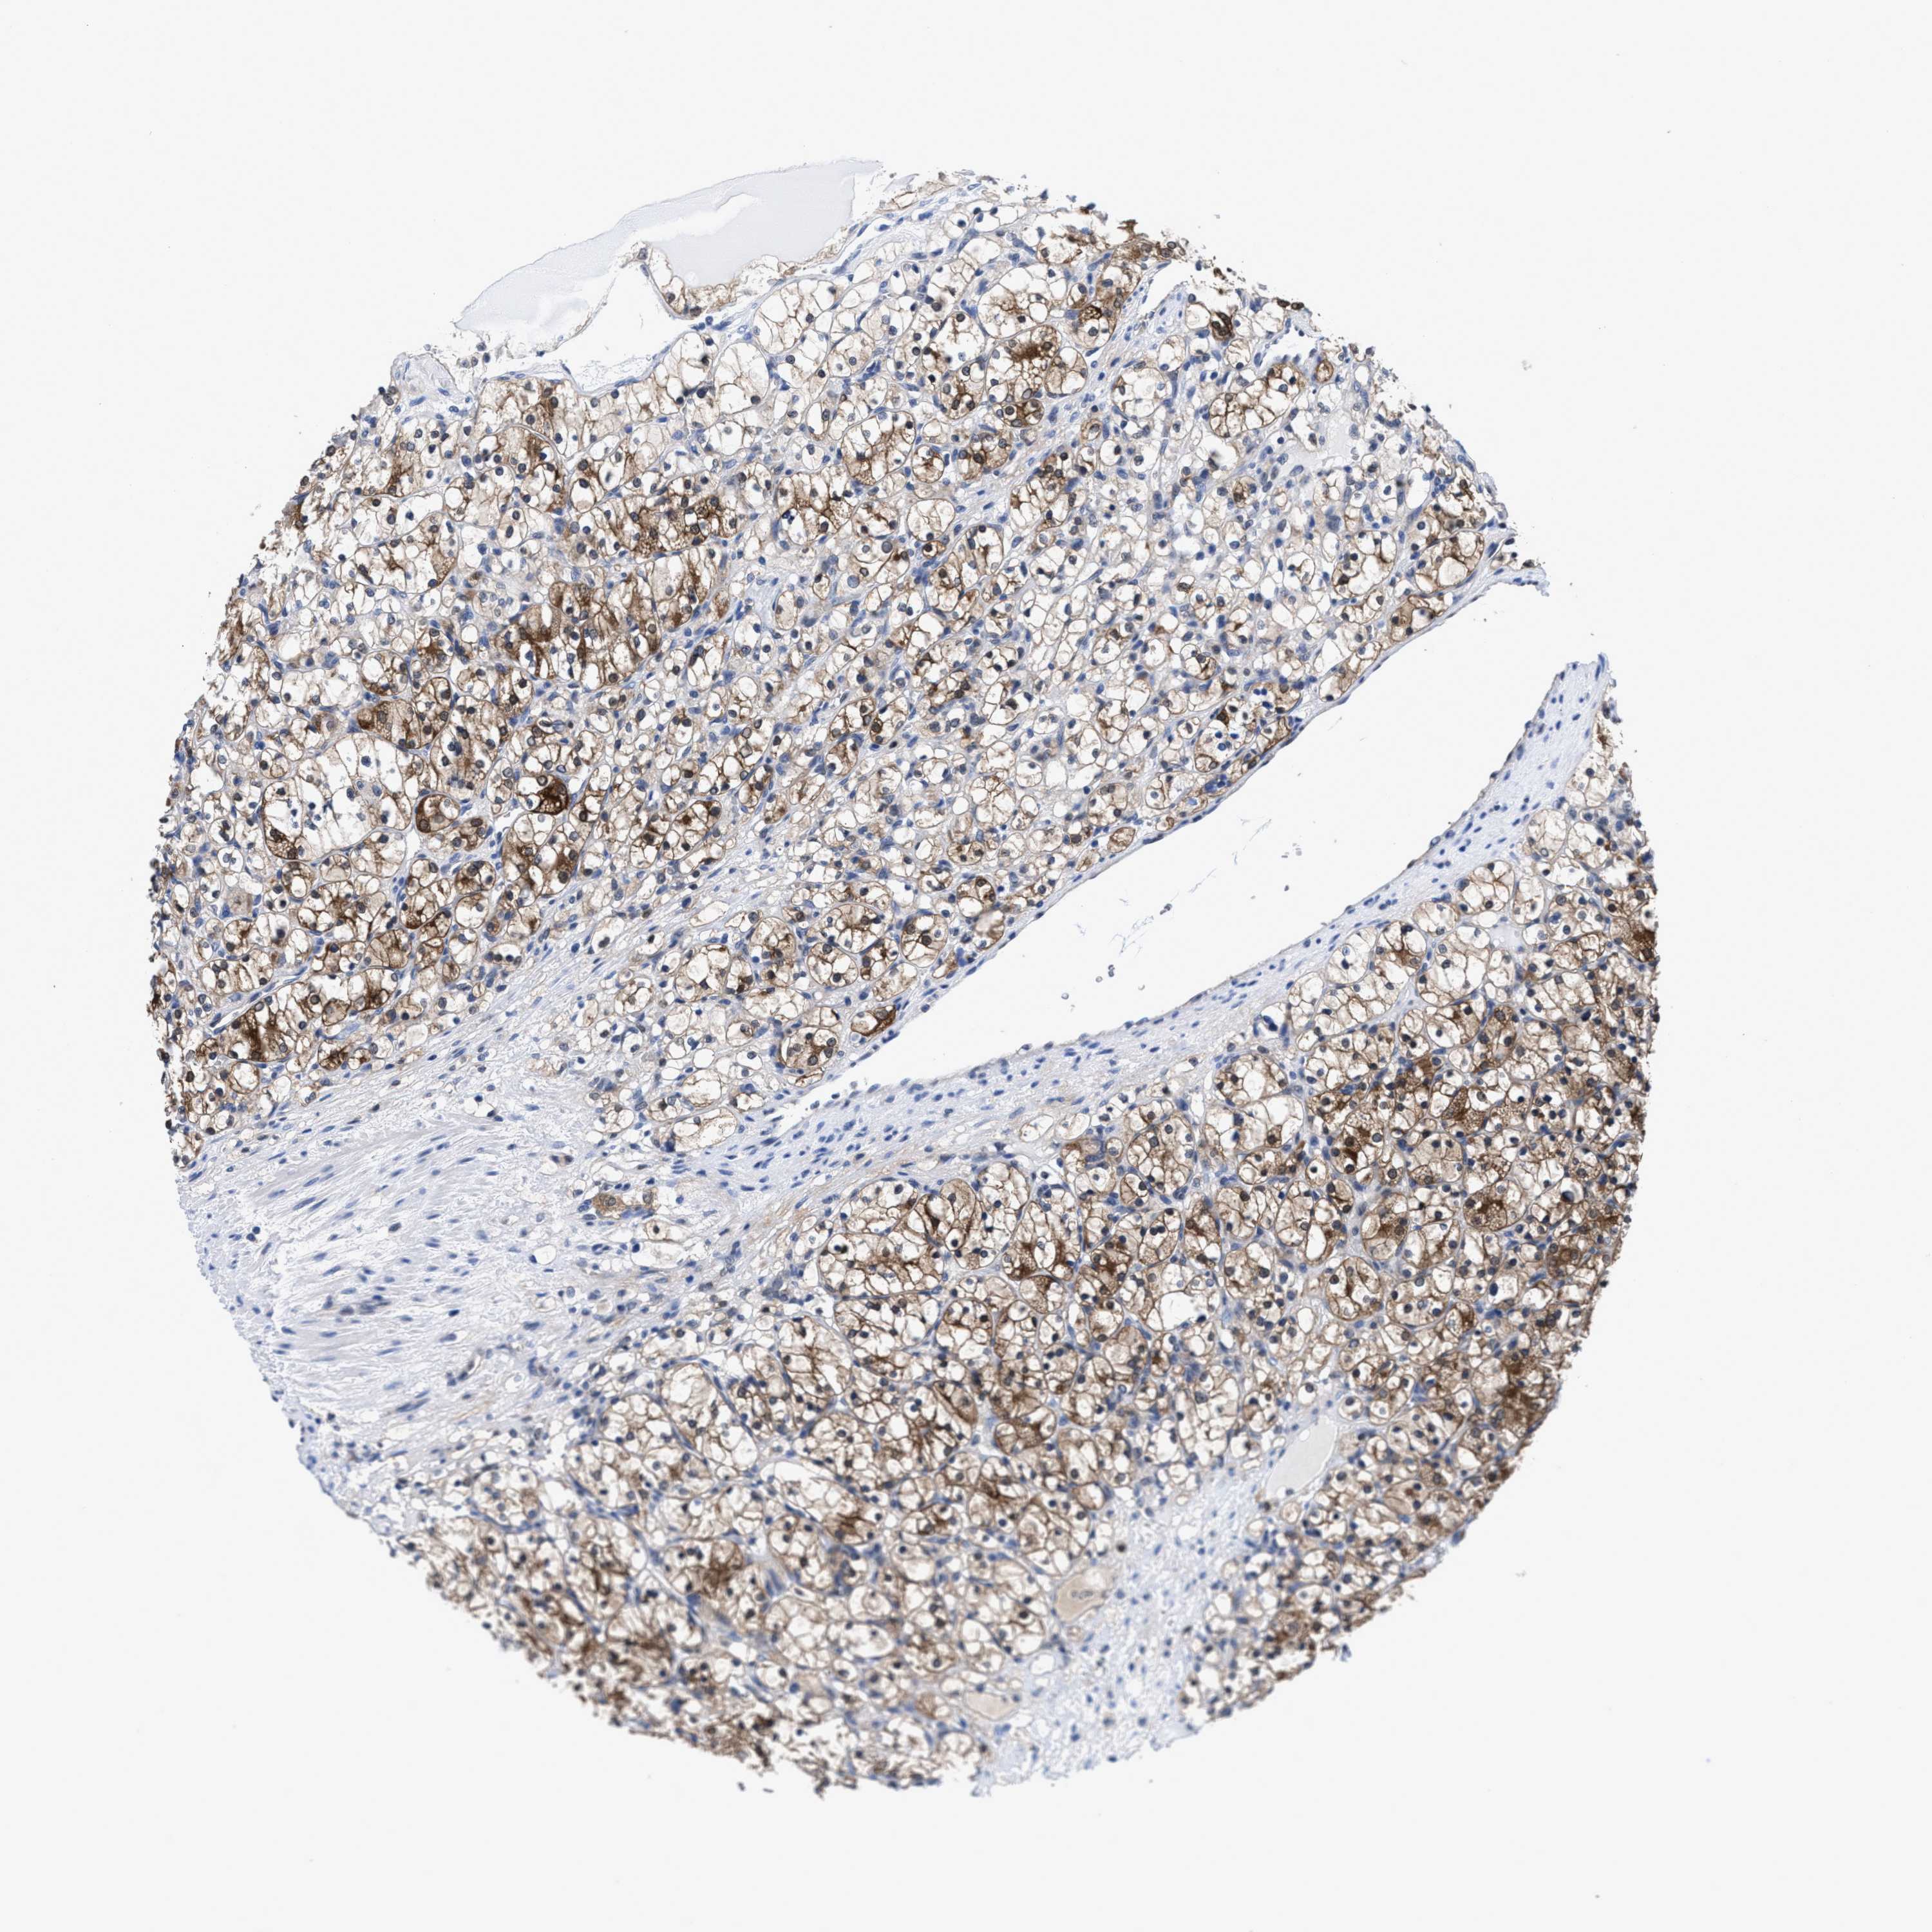

CANCER RENAL CANCER Show tissue menu

KICH TCGA KIRC TCGA KIRC VALIDATION KIRP TCGA PROTEIN RCC CPTAC PROTEIN EXPRESSION

KIDNEY RENAL CLEAR CELL CARCINOMA (VALIDATION) - Interactive survival scatter ploti

The Survival Scatter plot shows the clinical status (i.e. dead or alive) for all individuals in the patient cohort, based on the same data that underlies the corresponding Kaplan-Meier plots. Patients that are alive at last time for follow-up are shown in blue and patients who have died during the study are shown in red.

The x-axis shows the expression levels (FPKM) of the investigated gene in the tumor tissue at the time of diagnosis. The y-axis shows the follow-up time after diagnosis (years). Both axes are complimented with kernel density curves demonstrating the data density over the axes. The top density plot shows the expression levels (FPKM) distribution among dead (red) and alive patients (blue). The right density plot shows the data density of the survived years of dead patients with high and low expression levels respectively, stratified using the cutoff indicated by the vertical dashed line through the Survival Scatter plot. This cutoff is automatically defined based on the FPKM cutoff that minimizes the p-score. The cutoff can be changed by dragging the vertical line or by entering a cutoff value in the square labeled "Current cut-off".

Under the Survival Scatter plot the p-score landscape (black curve; left axis) is shown together with dead median separation (red curve; right axis). Dead median separation is the difference in median mRNA expression between patients who have died with high and low expression, respectively. It is calculated as follows: median FPKM expression of dead patients with high expression - median FPKM expression of dead patients with low expression. This is intended to aid the user in visually exploring custom cutoffs and the associated p-scores and dead median separation.

Individual patient data is displayed and can be filtered by clicking on one or more of the category buttons on the top of the page. Categories describing expression level and patient information include: high, low, alive, dead, female, male and tumor stages. The scale of the x-axis can be toggled between linear and log-scale by clicking on the "x log" button. Mouse-over function shows TCGA ID, patient information and mRNA expression (FPKM) for each patient.

& Survival analysisi

Kaplan-Meier plots summarize results from analysis of correlation between mRNA expression level and patient survival. Patients were divided based on level of expression into one of the two groups "low" (under cut off) or "high" (over cut off). X-axis shows time for survival (years) and y-axis shows the probability of survival, where 1.0 corresponds to 100 percent.

ACLY is not prognostic in Kidney Renal Clear Cell Carcinoma (validation)

Best expression cut offi

: 169.05

Median expressioni

: N/A

P scorei

N/A

5-year survival highi

For melanoma and glioma, 3-year survival is shown.

5-year survival lowi

TCGA RNA samplesi

RNA-seq data is reported as average FPKM (number Fragments Per Kilobase of exon per Million reads), generated by the The Cancer Genome Atlas (TCGA) .

Normal distribution across the dataset is visualized with box plots, shown as median and 25th and 75th percentiles. Points are displayed as outliers if they are above or below 1.5 times the interquartile range. FPKM values of the individual samples are presented next to the box plot.

Average pTPM 211.9

Number of samples 100